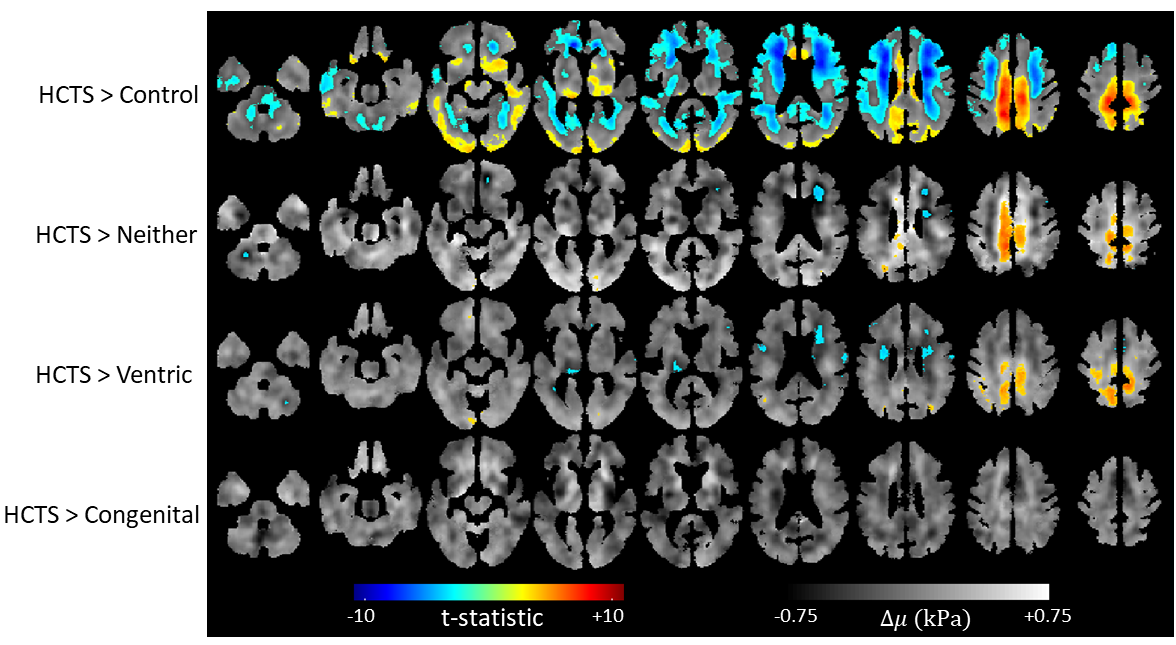

Group-wise mean stiffness maps show distinct patterns as shown in right panel of Figure 1. On the left of Figure 1, a boxplot is shown with a jitter plot of averaged stiffness values for each individual. Welch’s t-test and Wilcoxon rank sum test for stiffness between the groups show significant difference between the HCTS and the Control group (p<0.05). Damping ratio maps of the groups with the accompanying boxplots and jitter plots are shown in Figure 2. For the Welch’s t-test and the Wilcoxon rank sum test, the Ventric and the HCTS groups have significantly lower damping ratio values compared to the Control group with p<0.001. HCTS and Congenital groups have lower damping ratio compared to the Neither and the Control group respectively, with p<0.05. Figures 3 and 4 show difference and thresholded t-statistic maps (q<0.05) between the HCTS and each of the other groups. The number of significant voxels is reported in the respective figures. Leave-one-out cross validated correlation scores were calculated for all the cases with HCTS group as the reference. Correlation scores were calculated separately for the stiffness and the damping ratio. The pattern analysis plot with damping ratio scores in y-axis and stiffness scores in x-axis is shown in Figure 5.

Figure 3. Positive false discovery rate (pFDR) thresholded (q<0.05) t-statistic maps overlayed on voxel-wise calculated difference stiffness maps of each group compared to the HCTS group. The number of voxels that crossed the pFDR threshold were 493 for congenital, 9024 for Ventric, 6873 for Neither, and 92789 for Control.

Figure 4. Positive false discovery rate thresholded (q<0.05) t-statistics map overlayed on difference maps of groups compared to HCTS for the damping ratio. The number of voxels that crossed the pFDR threshold were 0 for congenital, 28693 for Ventric, 37618 for Neither, and 144022 for Control.